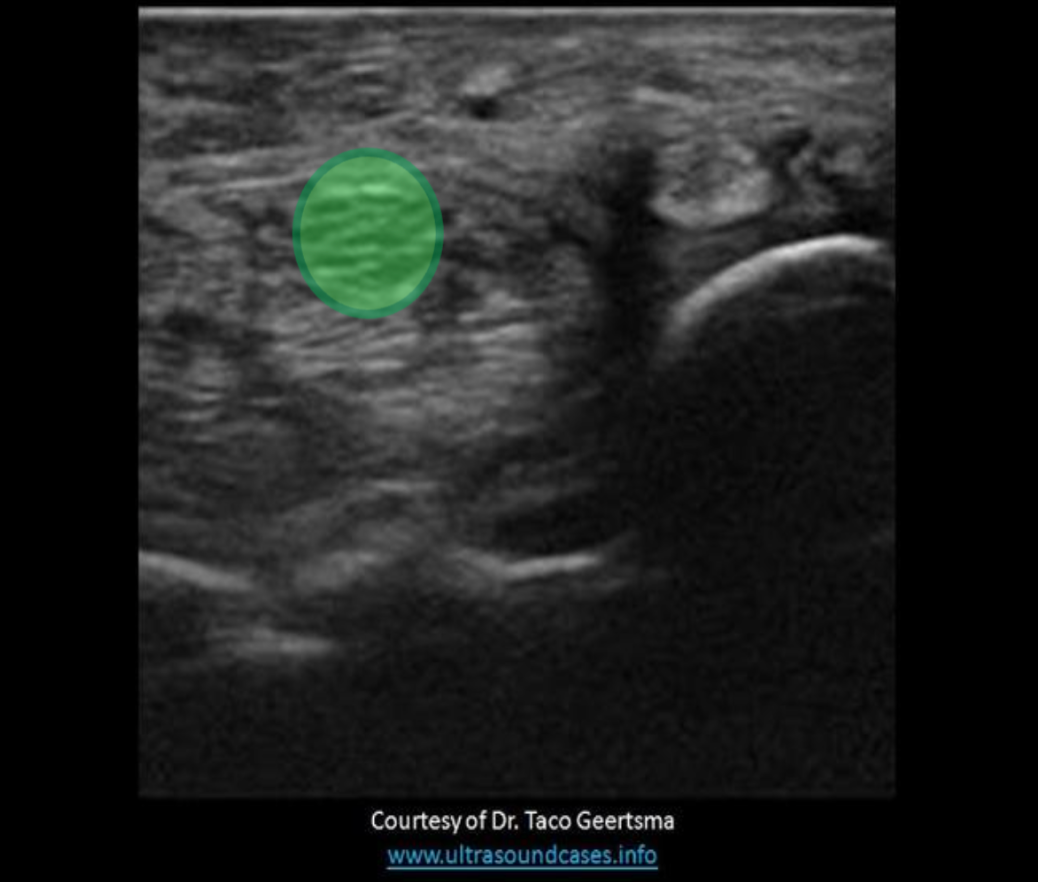

Which of the following vessels can be used to help locate the left adrenal gland?

C. splenic vein

The splenic artery and vein course between the tail of the pancreas and the left adrenal gland. Identifying these vessels can aid in identifying the left adrenal gland.